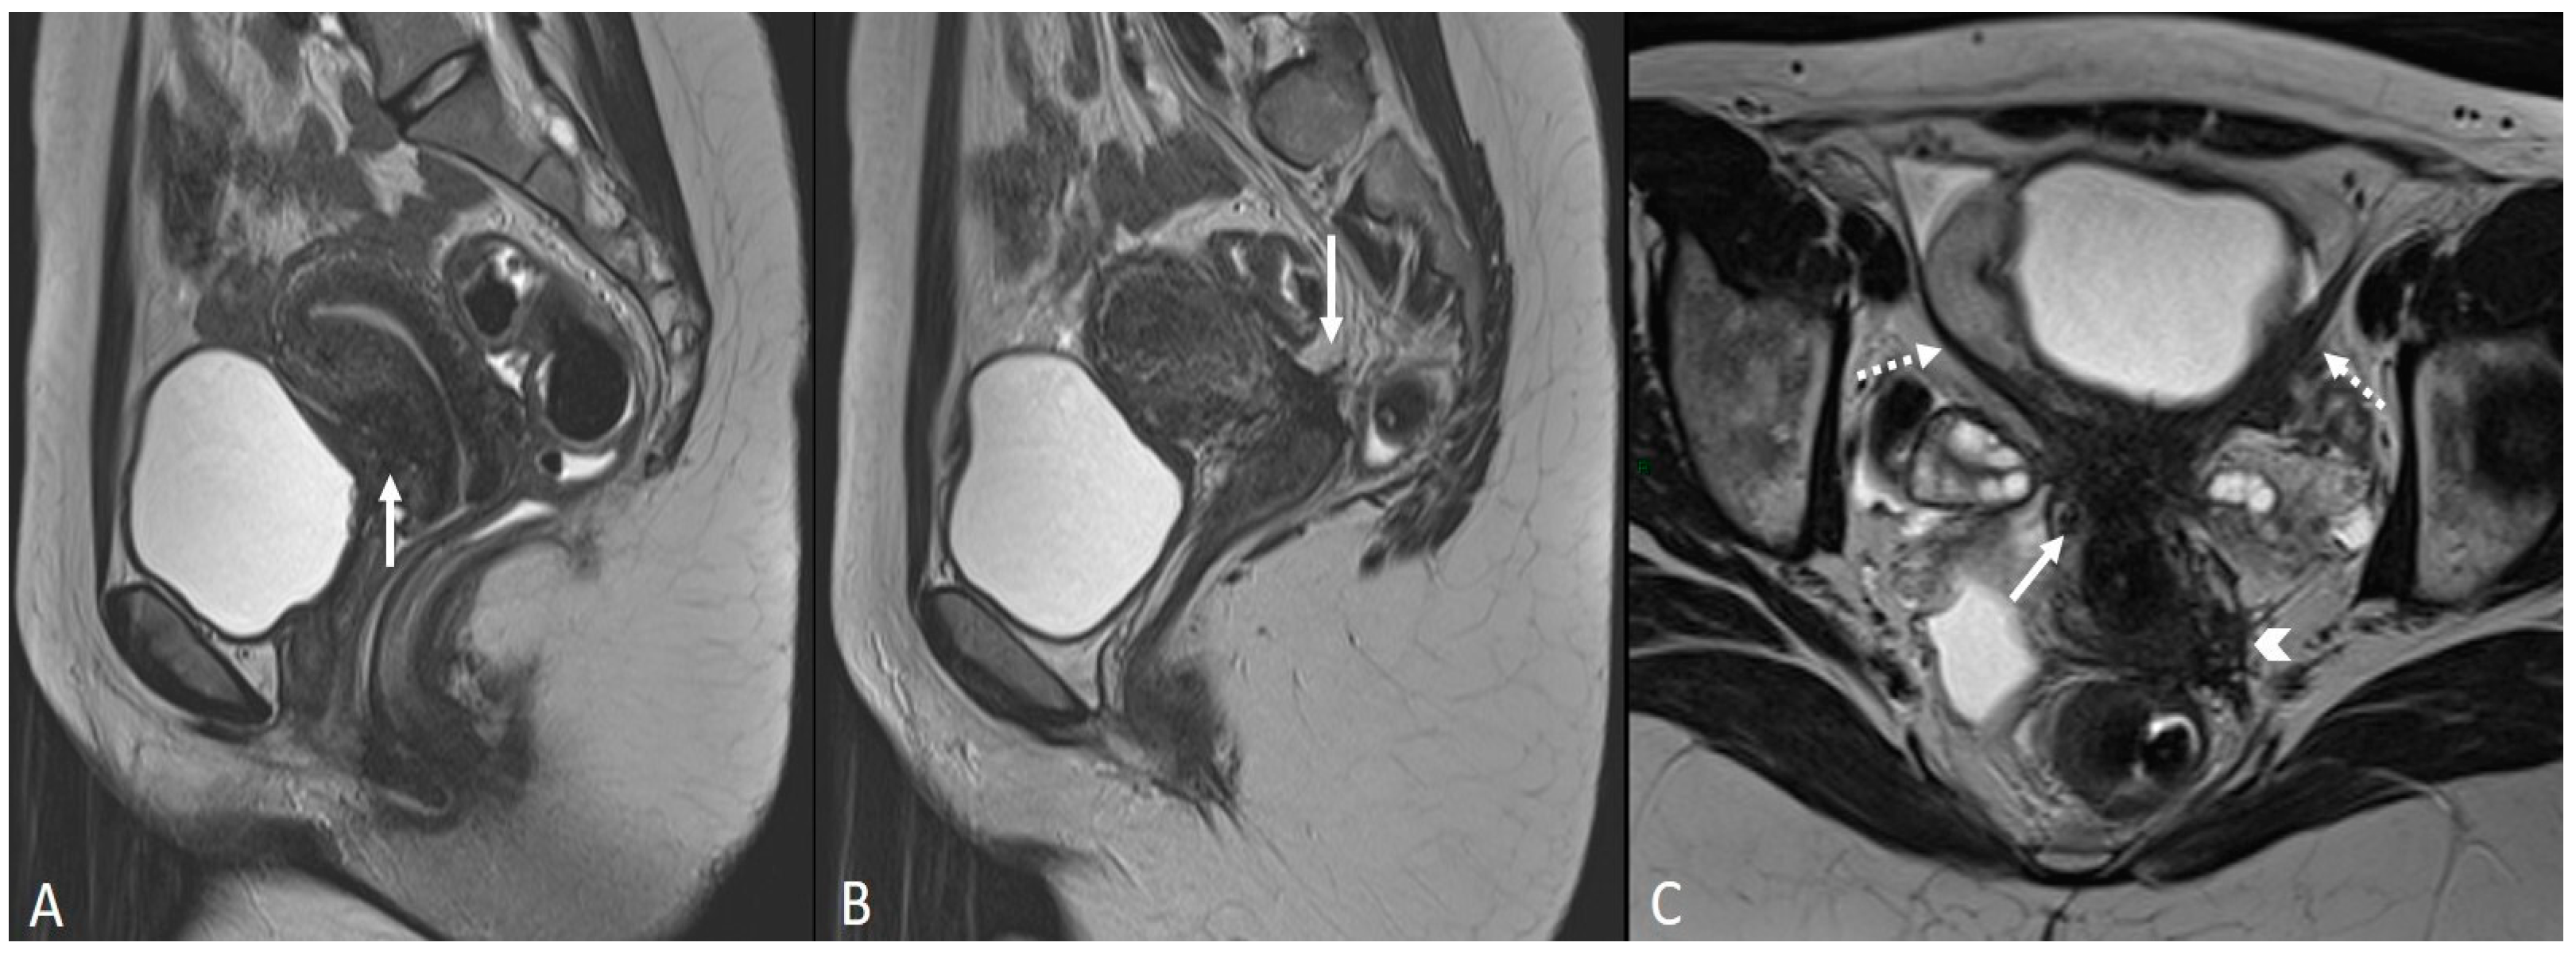

In other cases, the involvement of the round ligament can be appreciated as irregular contours with a nodular aspect [43] (Figure 2).

Figure 2.

Deep infiltrating endometriosis of the anterior and posterior compartments in 33-year-old female with dysmenorrhea, chronic pelvic pain, dyspareunia and dyschezia. (A) Sagittal T2WI. Evidence of external anterior adenomyosis and plaque of the vesico-uterine pouch (white arrow); (B) Sagittal T2WI. Retrocervical localization of DIE (white arrow); (C) Axial T2WI. Left uterosacral ligament (USL) localization (white arrowhead), plaque of vesico-uterine pouch (white arrow) with involvement of the round ligaments, particularly on the left (white dotted arrows), and adhesions with the ovaries (retraction of the broad ligaments).

The surgical approach can vary according to the proximal or distal involvement [39].

Involvement of the proximal portion of ligaments (distance less than 2 cm from the cervix) may, in some cases, be associated with thickening at the level of the torus uterinus; in such cases, it is essential to report any mass or thickening in the upper portion of the posterior cervix, as this could cause the surgeon to proceed with a laparoscopic trans-vaginal approach [7] (Figure 2, Figure 3 and Figure 4).

Figure 3.

Right uterosacral ligament localization in a 43-year-old female. The right uterosacral ligament appears thickened at uterine insertion (white arrow).

Figure 4.

Retrocervical endometriosis plaque, intestinal localization, kissing ovaries with bilateral ovarian endometriomas. (A,B) Axial T2WI; (C) Coronal T2WI. Hypointense retrocervical plaque (white arrowhead in (A)) localized in the uterine torus with involvement of the utero-sacral ligaments. Adhesions involve both ovaries with bilateral endometriomas (white arrows), which are prolapsed in a retro-uterine position and adhered to the utero-sacral ligaments and the recto-sigmoid junction. There is also an eccentric anterior parietal thickening in the recto-sigmoid junction suggestive of intestinal endometriosis lesion (white dotted arrow in (A)).